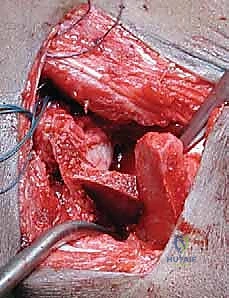

4. الرد المفتوح (إن لزم الأمر):

إذا كان الورك مخلوعاً، يتم تنظيف التجويف الحقي من أي أنسجة ليفية أو دهنية تعيق دخول رأس الفخذ. ثم يتم إرجاع رأس الفخذ إلى مكانه الطبيعي برفق.

5. إجراء القطع العظمي (بيمبرتون أو ديجا):

باستخدام أدوات جراحية دقيقة جداً، يتم إجراء القطع العظمي في الحوض وثني سقف الحُق لتغطية رأس الفخذ بالزاوية المثالية التي تم التخطيط لها.

6. تثبيت المفصل وإغلاق الجرح:

يتم أخذ طعم عظمي من حوض المريض ووضعه في شق القطع العظمي لتثبيت السقف في وضعه الجديد. في بعض الحالات، قد تُستخدم دبابيس معدنية (K-wires) لتثبيت إضافي مؤقت. يتم إغلاق الجرح بخيوط تجميلية تذوب تلقائياً.